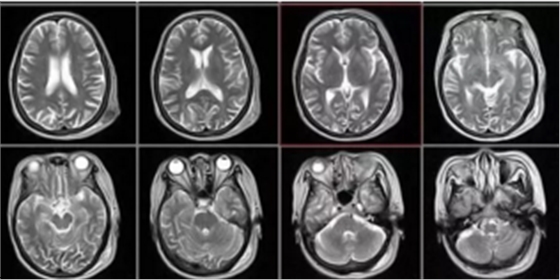

核磁共振

搖一搖再看

核磁共振機(jī)使用較強(qiáng)大的磁場(chǎng),使人體中所有水分子磁場(chǎng)的磁力線(xiàn)方向一致,這時(shí)磁共振機(jī)的磁場(chǎng)突然消失,身體中水分子的磁力線(xiàn)方向,突然恢復(fù)到原來(lái)隨意排列的 狀態(tài)。簡(jiǎn)單說(shuō),就相當(dāng)于用手搖一搖,讓水分子振動(dòng)起來(lái),再平靜下來(lái),感受一下里面的振動(dòng)。所以,核磁共振也被戲說(shuō)為是搖搖看的檢查。

2、頸椎腰椎——最佳選核磁,次選CT